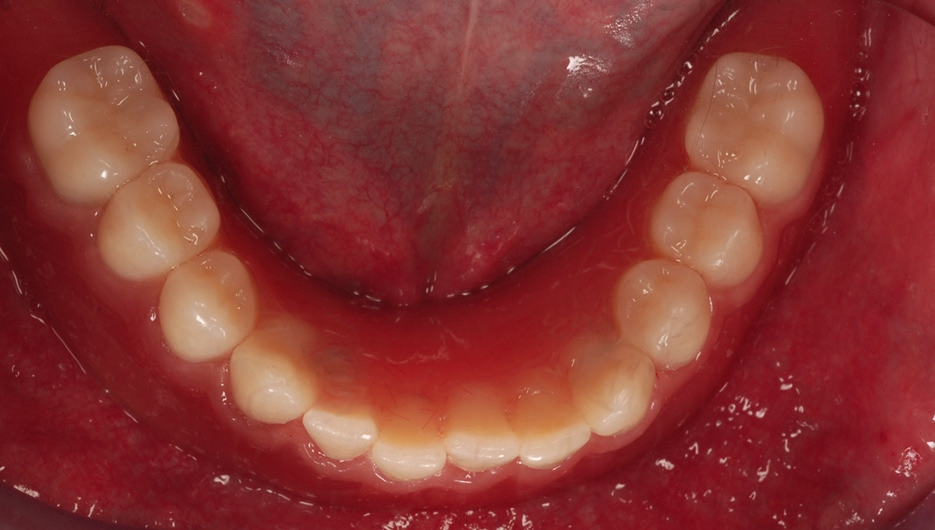

In unserem Patientenfall waren die Implantate annähernd parallel positioniert worden, so dass keine großen Abweichungen der Implantatachsen bestanden (Abb. 10). Es war ausreichend intermaxillärer Raum vorhanden und wir konnten den Patienten mit einer auf Kugelkopf-Attachments fixierten Unterkiefer-Cover denture Prothese versorgen. Das klinische Ergebnis war für Behandler und Patient gleichermaßen in optischer und funktioneller Hinsicht sehr zufriedenstellend (Abb. 11 und 12).